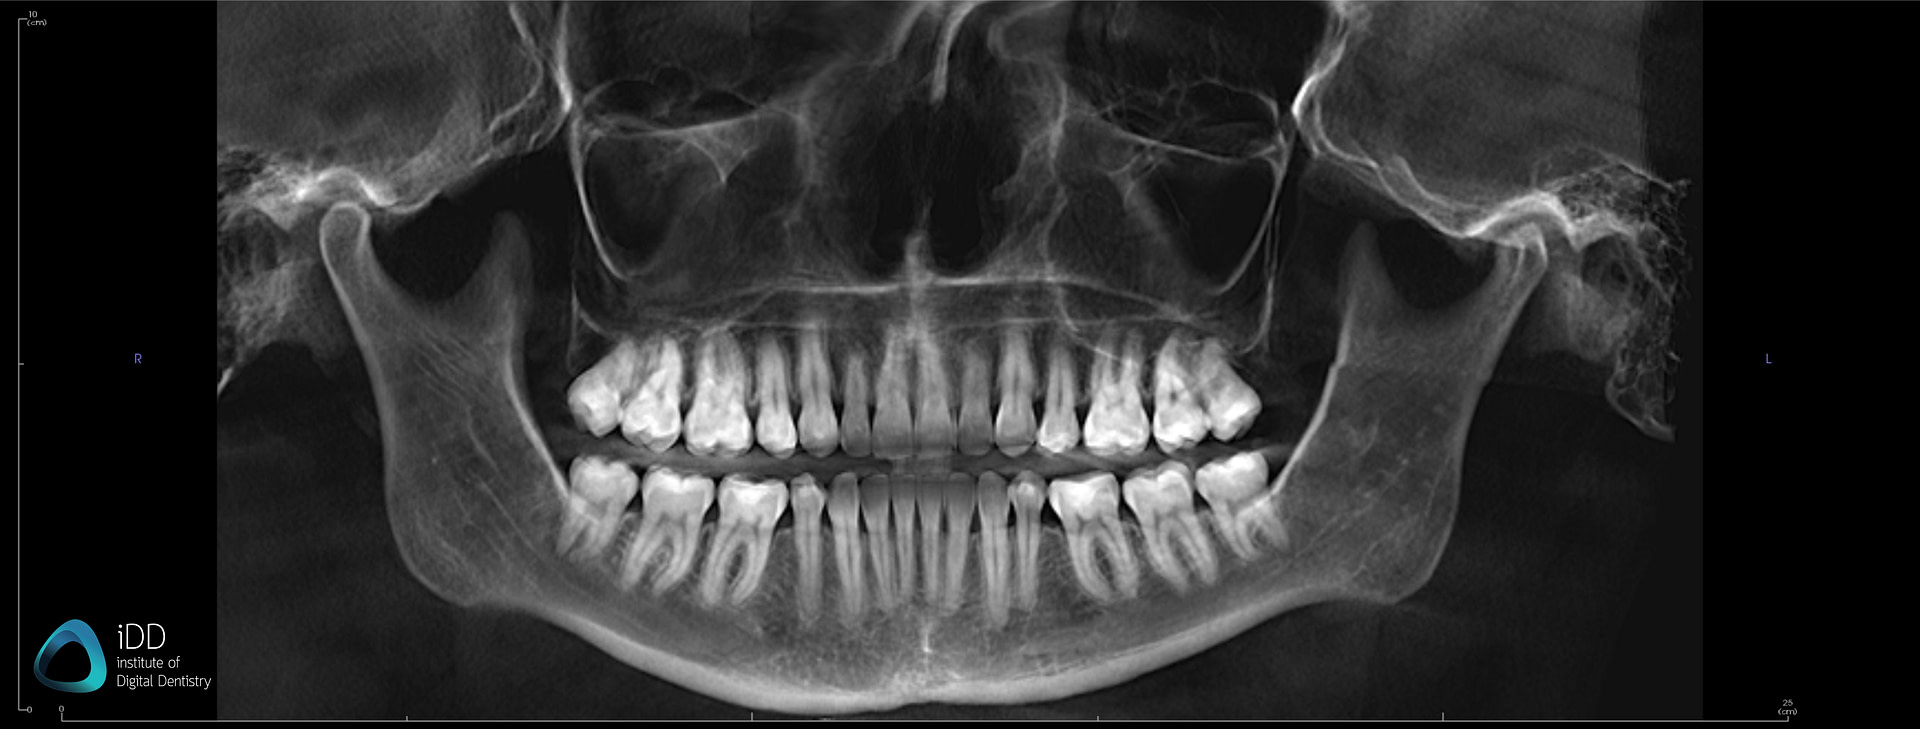

Panoramic image taken from a patient's CBCT.

These scans generate various file formats that carry a wealth of information, integral to dental diagnosis and treatment planning. In scenarios such as implant planning, endodontics, maxillofacial surgery, and orthodontics, traditional 2D images often fall short of providing the necessary depth of information. That's where CBCT comes in, filling the gap and enhancing diagnostic accuracy and precision.

CBCT files play a significant role in dental diagnosis. As CBCT files are digital in nature, they consist of a collection of 250 to 300 2D images to create a 3D volume reconstruction of the data.

This collection of images provides comprehensive information by obtaining a 3D image of the jaw to assess bone volume, bone density, and bone quality to determine the best treatment outcome and observe the patient's prognosis over time.